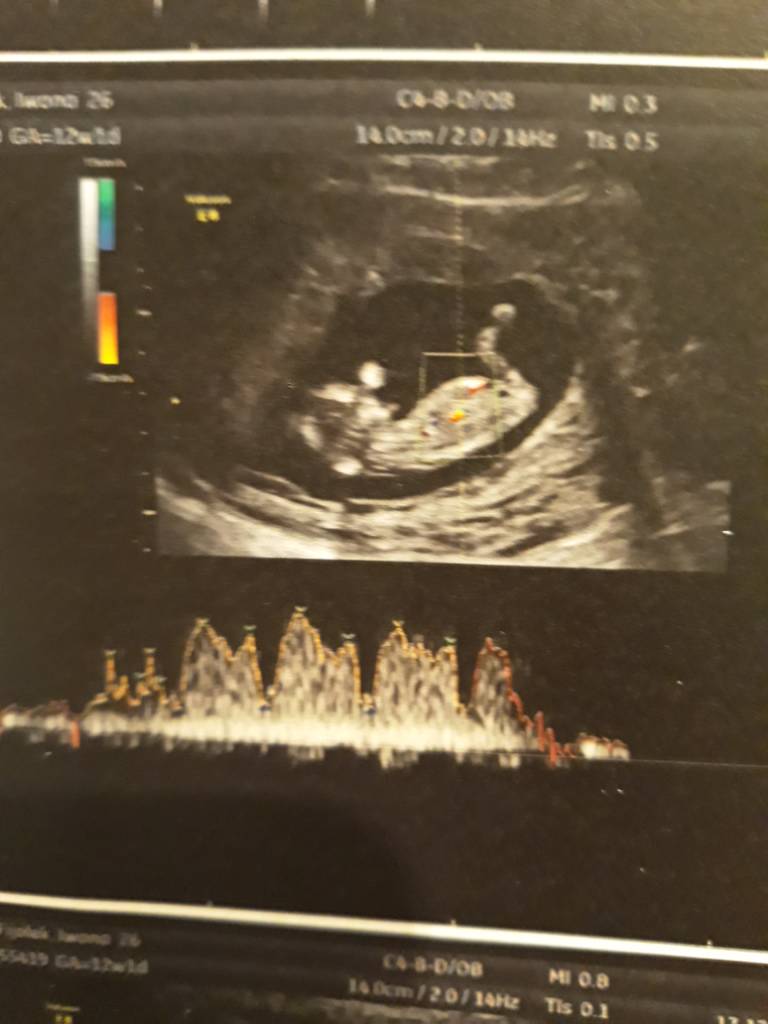

A no i dolaczam zdjecia moich Kabanoskow - jeden leniuszek ladnie pozowal a drugi wyglada jak kosmita bo sie ruszal , dzis tez do mnie machal !

A no i dolaczam zdjecia moich Kabanoskow - jeden leniuszek ladnie pozowal a drugi wyglada jak kosmita bo sie ruszal , dzis tez do mnie machal !ale z dzis zdjec nie mam bo to byl szybki.poglad ze wzgledu na upadek... aaa plecy bola ;(

Pytałam tez lekarki czy to zle ze jedno lozysko z przodu a drugie stylu i stwierdzila, ze to bardzo dobrze bo im mniej maja ze soba wspolne i sa odizolowani nawet stronami lozyska tym lepiej dla nich. Uf...

Pytałam tez lekarki czy to zle ze jedno lozysko z przodu a drugie stylu i stwierdzila, ze to bardzo dobrze bo im mniej maja ze soba wspolne i sa odizolowani nawet stronami lozyska tym lepiej dla nich. Uf...Zobacz załącznik 926248Zobacz załącznik 926249Zobacz załącznik 926250Zobacz załącznik 926251Zobacz załącznik 926252